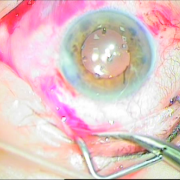

H επιστημονική μας ομάδα έχει την ικανότητα αντιμετώπισης όλων των τύπων των καταρρακτών, απλών, με μικρή κόρη, υπερώριμων, με φακοδόνηση, μετά από Laser μυωπίας και υπερμετρωπίας, καθώς και σοβαρότερων επιλεγμένων περιπτώσεων.

Οι σύγχρονες μικροχειρουργικές τεχνικές αποβλέπουν στον ελάχιστο τραυματισμό του οφθαλμού και στην τοποθέτηση του τεχνητού ενδοφακού στην φυσική του θέση που είναι ο οπίσθιος θάλαμος. Οι ασθενείς απολαμβάνουν τα πλεονεκτήματα των επεμβάσεων μικρής τομής χωρίς ράμματα, με άμεση αποκατάσταση της όρασης και χωρίς μετεγχειρητικό αστιγματισμό.

καταρράκτης με τραυματική

ρήξη οπ.περιφάκιου από

έγγχυση ANTIVGEF παράγοντα

του οπ. περιφάκιου